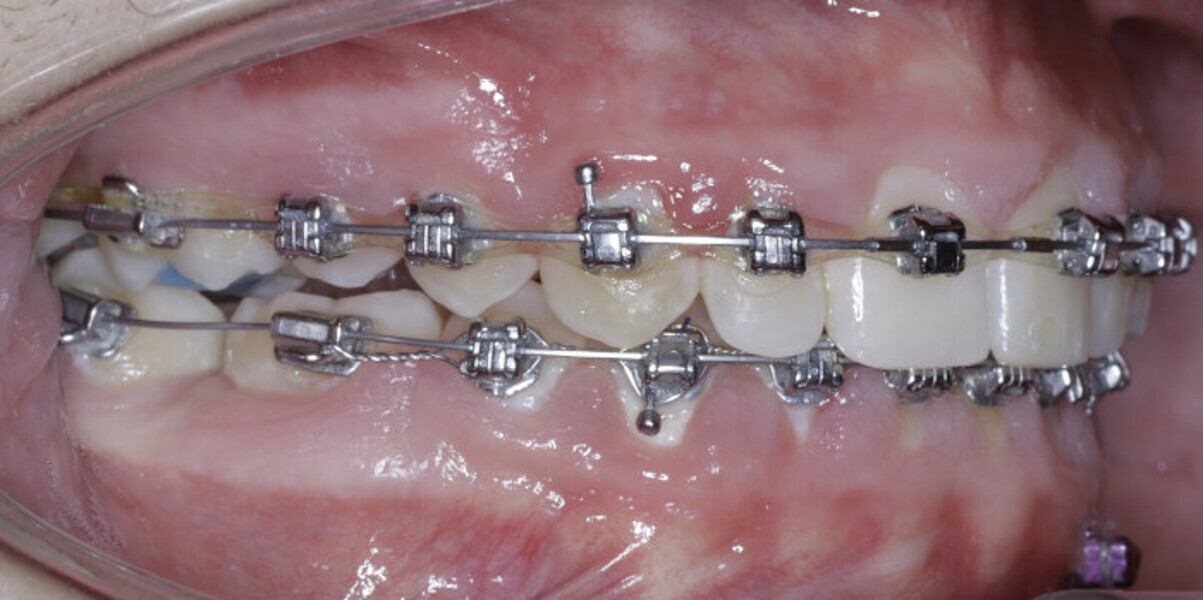

New Age orthodontics and orthopaedics with temporary anchorage devices